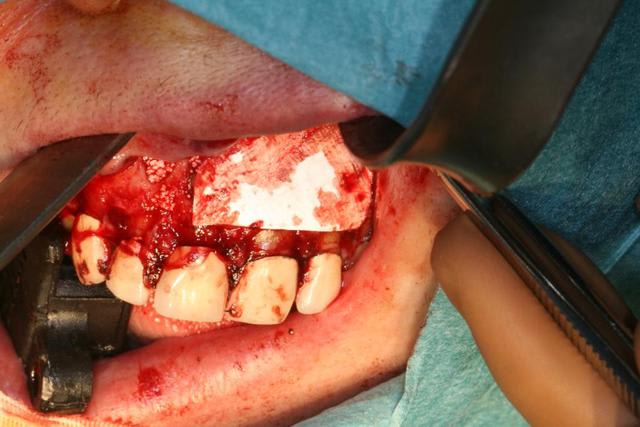

Ce matin j'ai opéré une patiente pour un bon kyste maxillaire d'origine dentaire très certainement et quelques petits sur d'autres dents.

Dans un premier temps j'ai disséqué le kyste qui a détruit le plancher des fosses nasales et le mur palatin.

Dans un second temps j'ai fait des préparations à rétro sur les dents causales (11-21-22-14). Puis j'ai réalisé un collage à rétro car les tenons atteignaient les apex.

Enfin j'ai isolé par des membranes Biogide et comblé avec du bétaTCP.